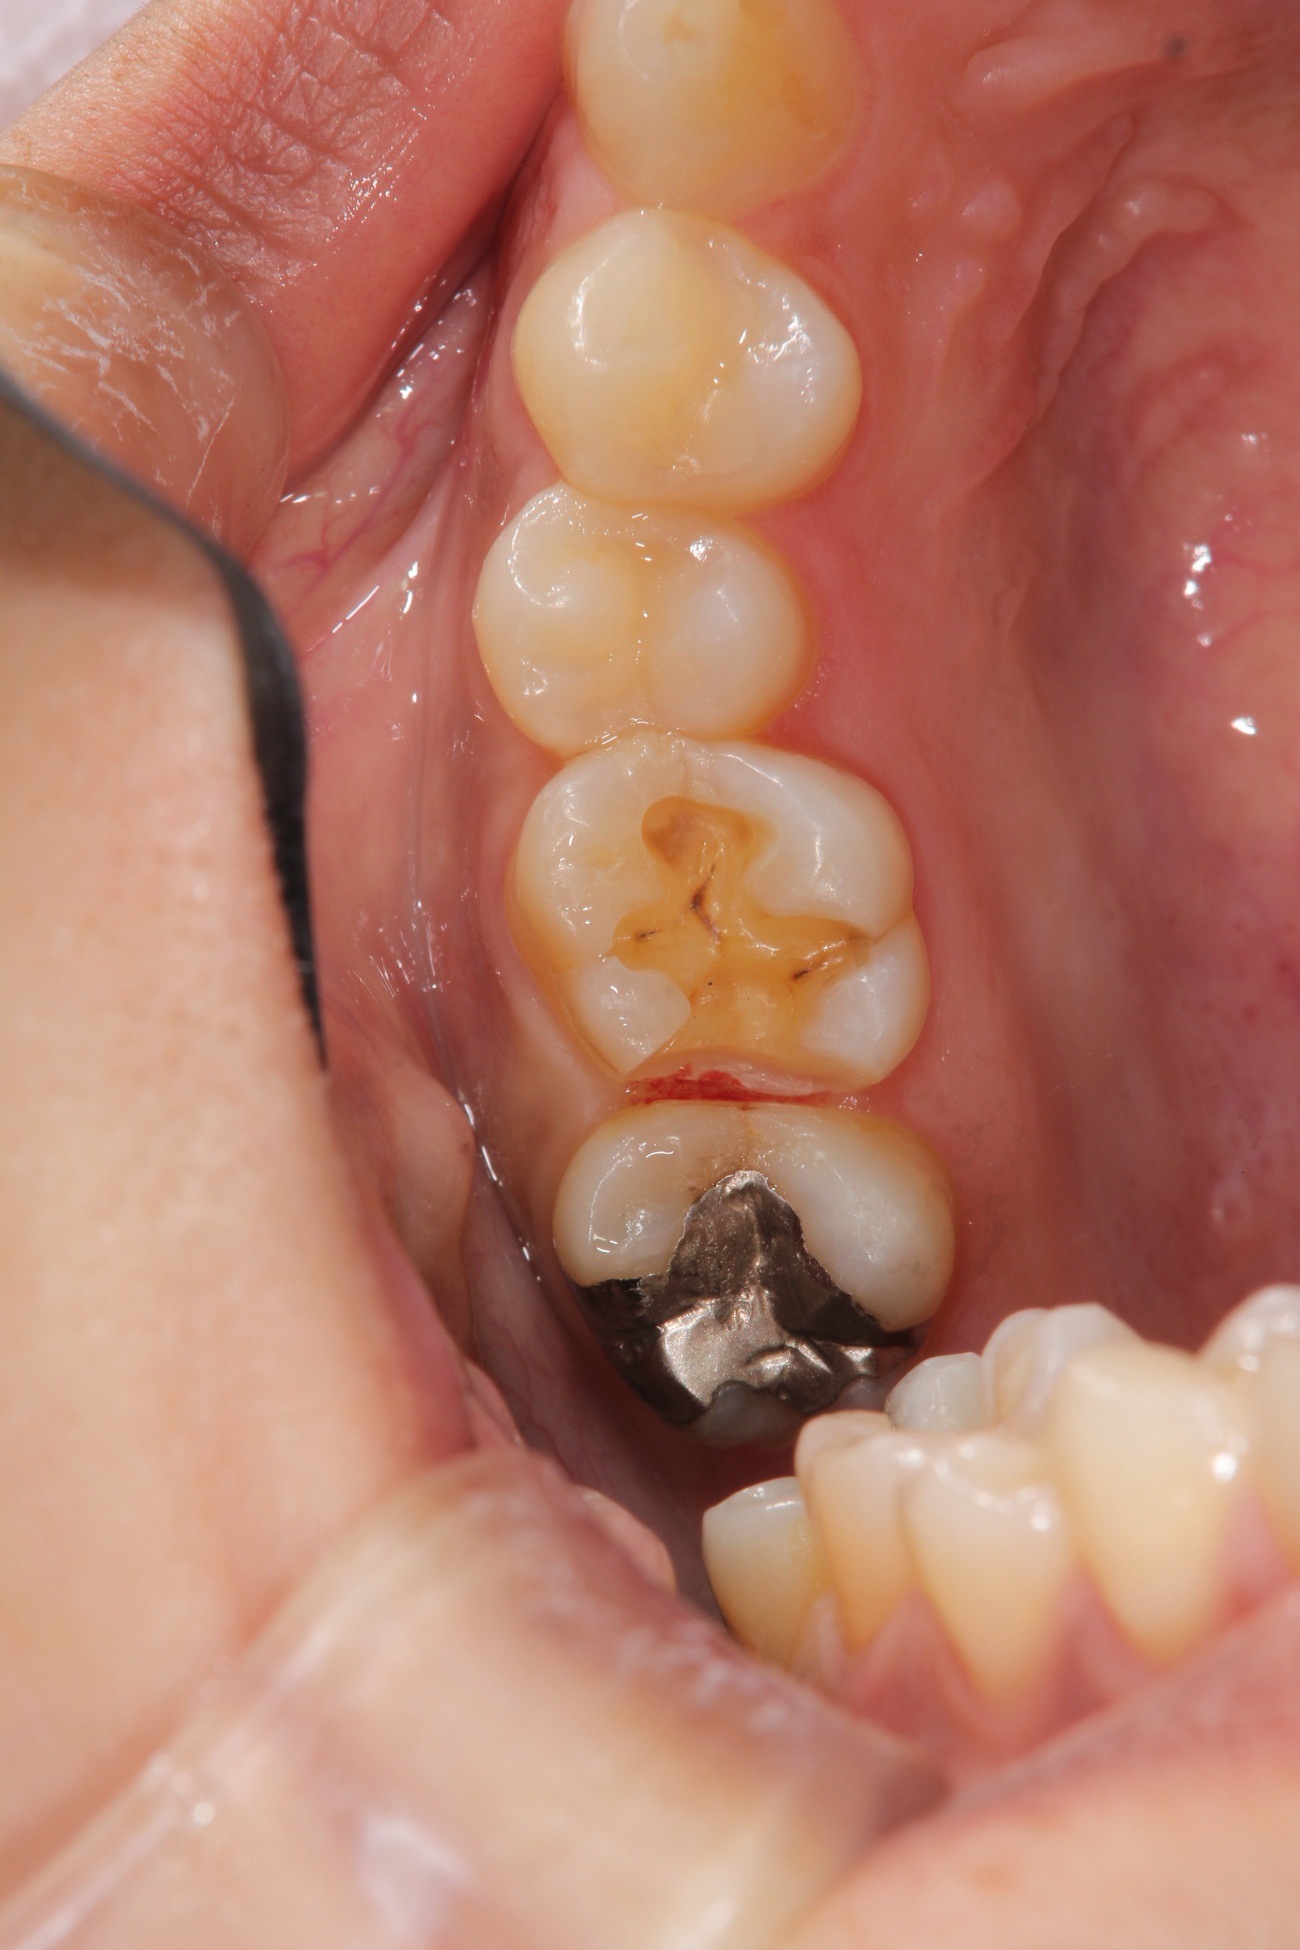

オールセラミックインレーの術前術後です。左の写真は削った後です。歯の周りに黒い線が見えますが、圧排糸という歯と歯ぐきの境目を明瞭にする為の物です。右が術後ですが、歯の色と同化しており、ほとんど区別がつきません。また、汚れをはじく性質を持っているため、歯ぐきに炎症が起きにくいです。変色が起きないため半永久的に、この状態を保ってくれます。

銀歯を外してセラミックインレーを装着した状態です。

セラミックインレー

費用11万円

リスクとして歯を削る量が多いため痛みが出る可能性と強い力によって割れる可能性がある。